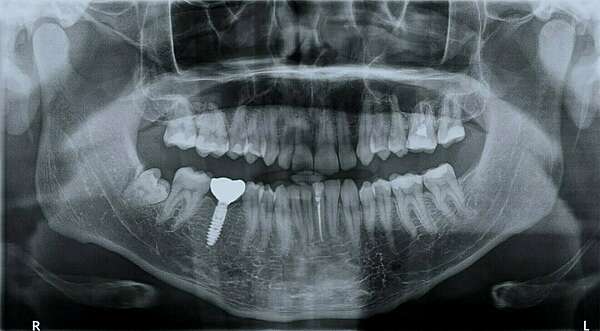

Un panoramique dentaire permet de réaliser une radiographie panoramique des dents et des mâchoires.